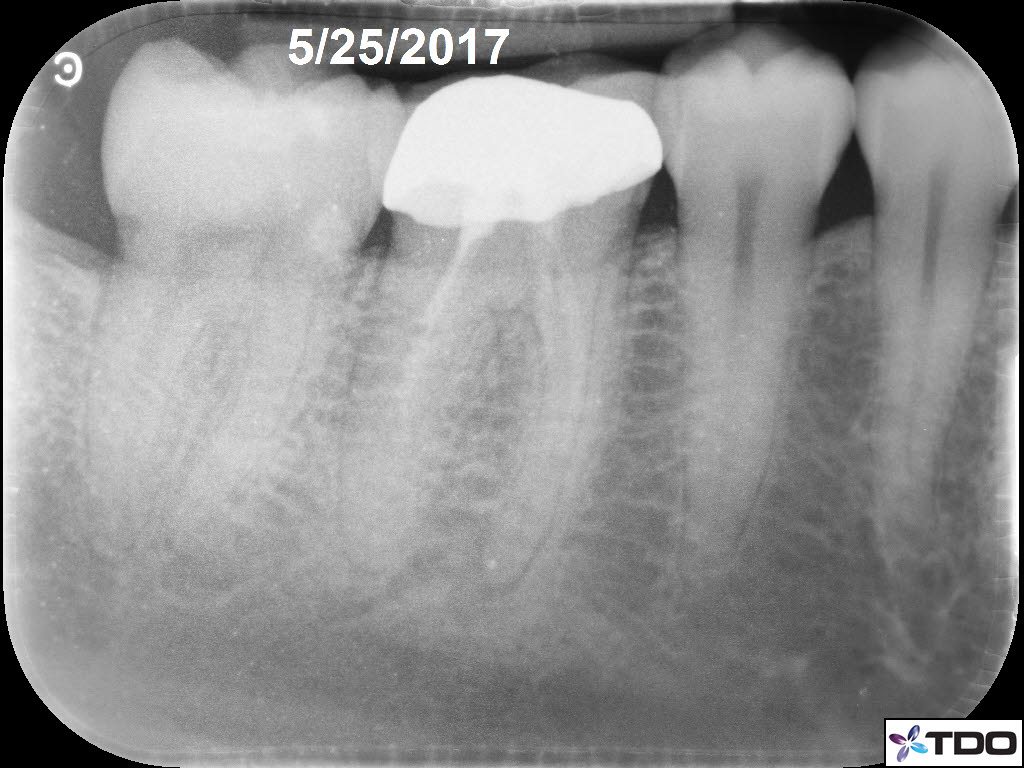

In the hierarchy of dentin conservation the existing restorative has the lowest priority and it quite frankly gets in the way of our access to the root canal system. But, after practicing directed dentin conservation for a while, you sometimes get lucky. The patient is 40yo. She was symptomatic at the time of treatment and interestingly the mesiobuccal canal was partially vital while the mesiolingual, distobuccal and distolingual canals were partially necrotic. She was asymptomatic at the completion visit as well as at the follow-up appointments.

Hi Gergely. The crown was less than two weeks old when the patient was first seen in my office. The previous crown was 15 yrs old and was seldom sensitive; the RD replaced the crown due to an “open margin.” Heat/cold sensitivity ensued after the crown prep. Four days after the permanent crown was cemented the patient woke up with severe throbbing pain and the temp sensitivity became worse. When she presented to my office she reported severe biting tenderness and tender submandibular lymph nodes.